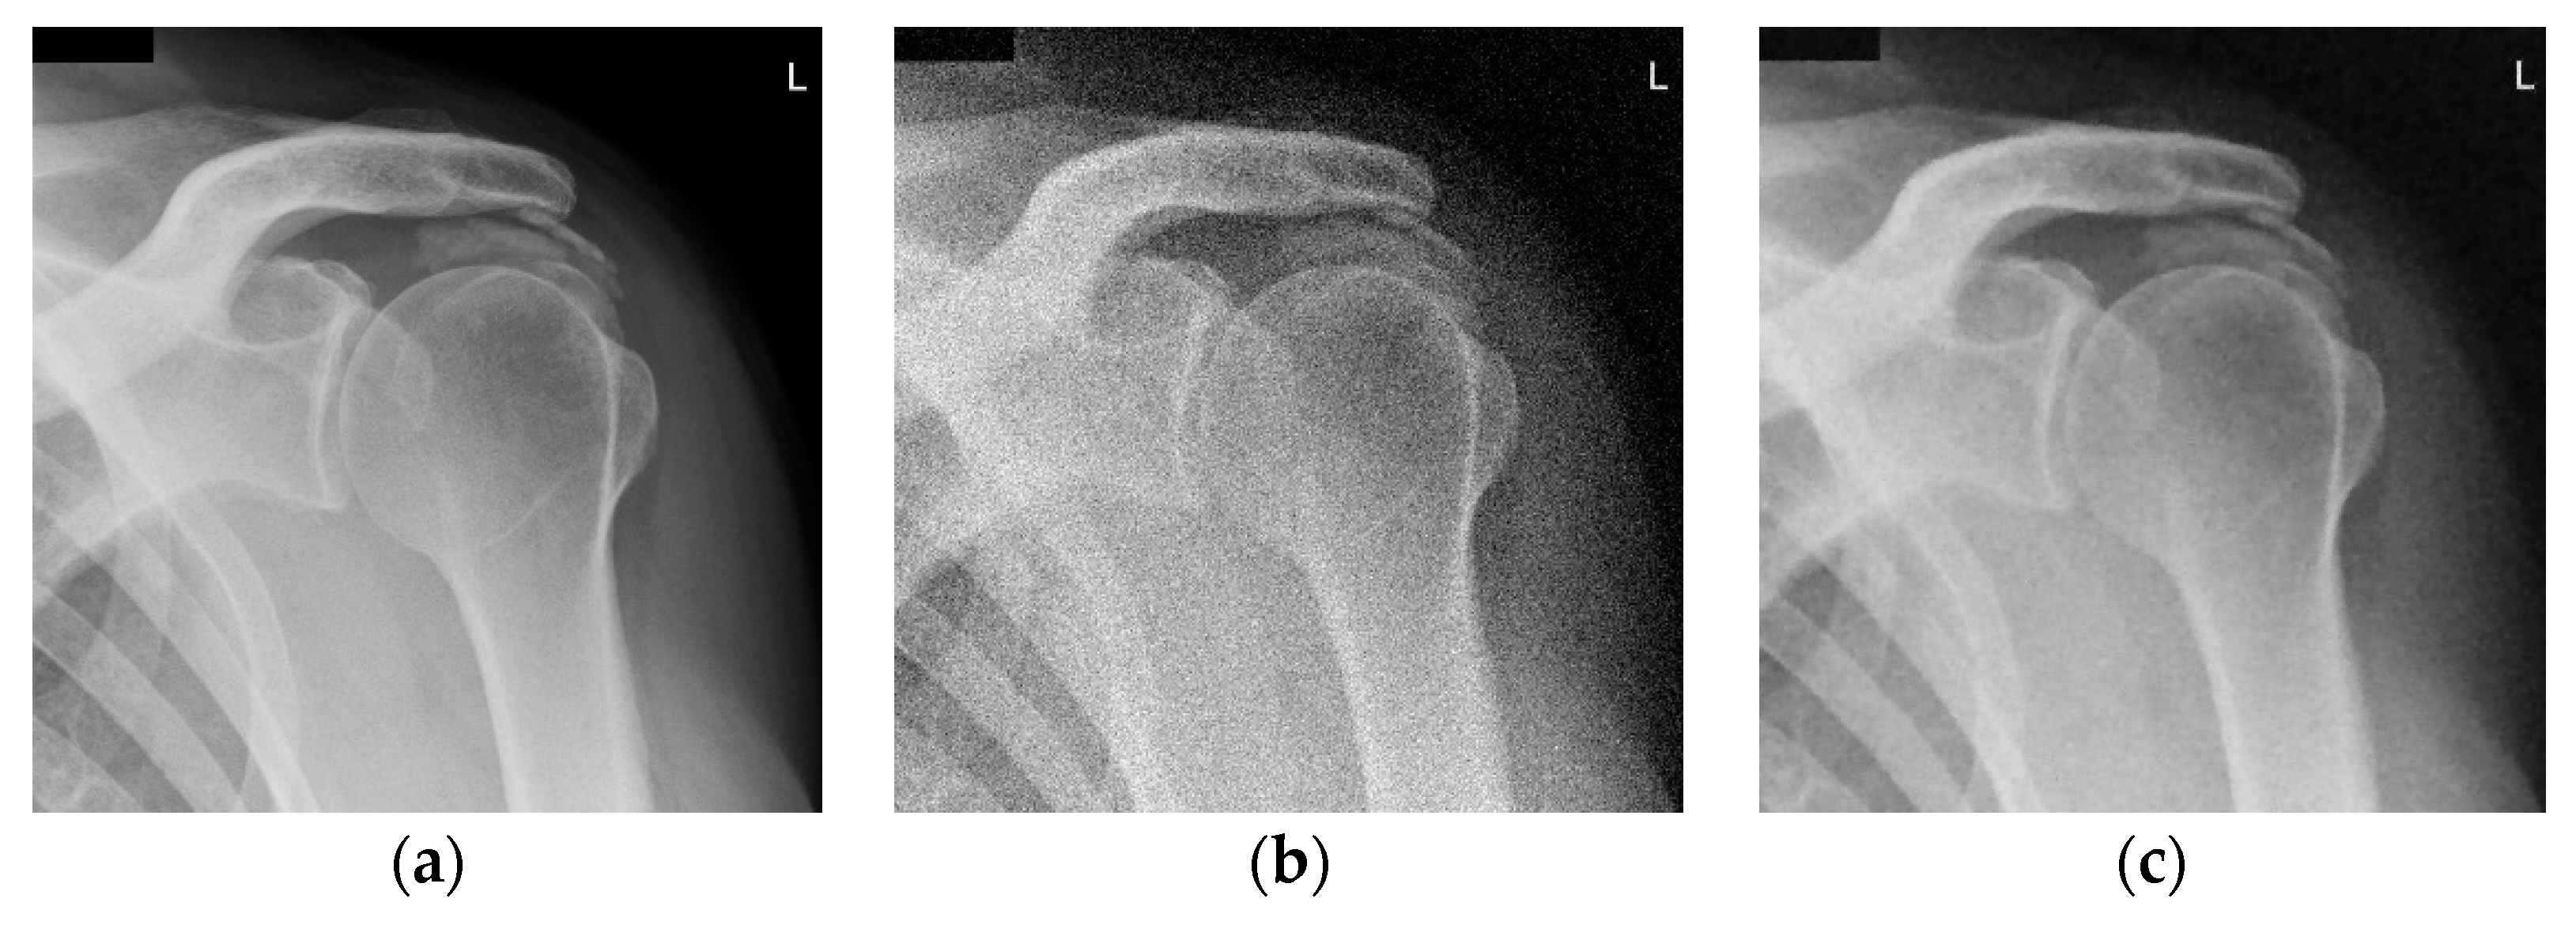

The results for the second test image (chest X-ray image with the resolution 2431 × 1782) are given in Figure 4. Namely, Figure 4a,b shows the noise-free and the noisy image (also corrupted with AWGN with σ = 25), respectively. Figure 4c–e present denoised images obtained using the proposed 2D LPA-RICI algorithm with quadrilateral, octagonal and hexadecagonal regions, respectively.

Figure 4.

Chest X-ray scan. (a) Original noise-free image; (b) Noisy image (AWGN with σ = 25); (c) Image denoised using the 2D LPA-RICI method (quadrilateral region, Г = 1.8, Rc = 0.8); (d) Image denoised using the 2D LPA-RICI method (octagonal region, Г = 1.8, Rc = 0.8); (e) Image denoised using the 2D LPA-RICI method (hexadecagonal region, Г = 1.8, Rc = 0.8); (f) Image denoised using Gaussian smoothing filters; (g) Image denoised using total variation denoising.

The PSNR results for denoised chest X-ray images are found in Table 3. As it can be seen from Table 3, the proposed 2D LPA-RICI method (as it was the case for the shoulder X-ray image) outperformed fixed size 2D filtering in all cases. Furthermore, the RICI based denoising outperformed Gaussian smoothing filters and total variation denoising when quadrilateral and octagonal regions were used.

Table 4 gives PSNR improvements for chest X-ray scan denoised using the 2D LAP-RICI method compared to noisy images and images denoised using the fixed size filtering, Gaussian smoothing filters and the total variation method, respectively. Namely, the LPA-RICI method enhanced denoised image quality, both visually and in terms of the PSNR, by up to 9.40 dB when quadrilateral regions were used, by up to 10.23 dB when octagonal regions were used and by up to 5.25 dB when hexadecagonal regions were used (when compared to the noisy image PSNR). It also outperforms fixed size 2D median filtering in all cases, increasing the PSNR by up to 7.51 dB. In addition, the 2D LPA-RICI method outperformed the Gaussian smoothing filters by up to 5.35 dB when quadrilateral and octagonal regions were used. Furthermore, it also outperformed the total variation denoising increasing the PSNR by up to 3.30 dB (in case of the adaptive 2D quadrilateral and octagonal regions).